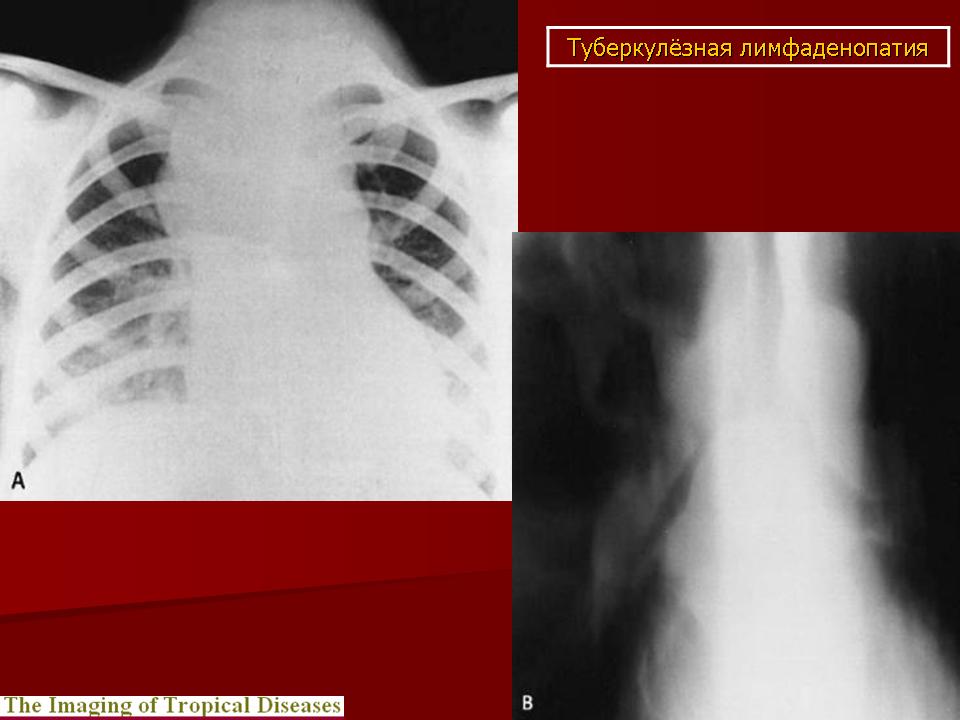

Различают инфильтративный, опухолевидный и малые формы туберкулеза внутригрудных лимфатических узлов. Опухолевидная форма проявляется увеличением размеров лимфатических узлов в результате воспалительной гиперплазии, что обнаруживается при рентгенологическом исследовании. Контуры лимфатических узлов на рентгенограмме и томограммах четкие. Инфильтративный туберкулез внутригрудных лимфатических узлов характеризуется не только увеличением узлов, но и развитием инфильтративных изменений в легочной ткани, в прикорневых ее отделах. Малые формы проявляются незначительным увеличением внутригрудных лимфатических узлов, что выявляется главным образом на томограммах с поперечным размазыванием в прямой или боковой проекциях. Этот вариант заболевания в последнее время встречается чаще, чем в прежние годы.

В современных условиях изменилась структура клинических форм туберкулеза, и появились нетипичные для повседневной практики его проявления. Повышенная восприимчивость к туберкулезу лиц, ранее не инфицированных микобактериями туберкулеза, способствует появлению туберкулеза внутригрудных лимфатических узлов (ТВЛУ) у взрослых. Неосложненное течение ТВЛУ у взрослых проявляется только рентгенологически односторонним или реже двусторонним увеличением различных групп внутригрудных лимфатических узлов. Неправильная оценка изменений во внутригрудных лимфатических узлах при туберкулезе ведет к распространению туберкулезного процесса на бронхи и легочную паренхиму. Возникают различной степени нарушения бронхиальной проходимости, которые сопровождаются развитием воспалительных изменений. Представляю наблюдение осложненного течения ТВЛУ у женщины 61 года, которая была направлена в РОНЦ с диагнозом: центральный рак правого легкого с ателектазом верхней доли. Рис. 1а, б. Верхняя доля правого легкого уменьшена в объеме, однородно уплотнена. Нижний контур доли вогнутый. Органы средостения в верхнем отделе умеренно смещены вправо. Диафрагма на стороне поражения расположена выше обычного. Рис. 2а, б, в, г. Компьютерные томограммы органов грудной клетки. На передней стенке правого главного бронха узелковые образования, перекрывающие частично просвет бронха. Верхнедолевой бронх нитевидно сужен. Верхняя доля правого легкого уменьшена в объеме, верхушечный и задний сегмент ателектазированы.

Неосложненное течение ТВЛУ у взрослых проявляется только рентгенологически односторонним или реже двусторонним увеличением различных групп внутригрудных лимфатических узлов.